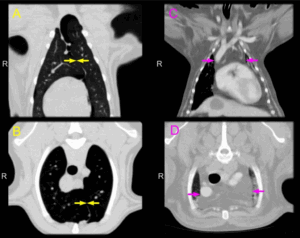

Более подробная диагностика лимфоузлов включает:

- УЗИ; ;

- КТ.

Увеличение тех, которые находятся в труднодоступных местах, можно диагностировать с помощью компьютерной или магнитно-резонансной томографии , ультразвукового исследование. Также всегда назначается общий анализ крови и мочи.